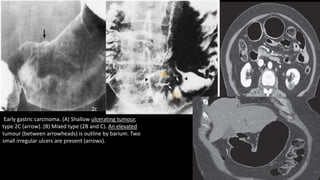

Early gastric carcinoma. (A) Shallow ulcerating tumour,

type 2C (arrow). (B) Mixed type (2B and C). An elevated

tumour (between arrowheads) is outline by barium. Two

small irregular ulcers are present (arrows).

2c

2B